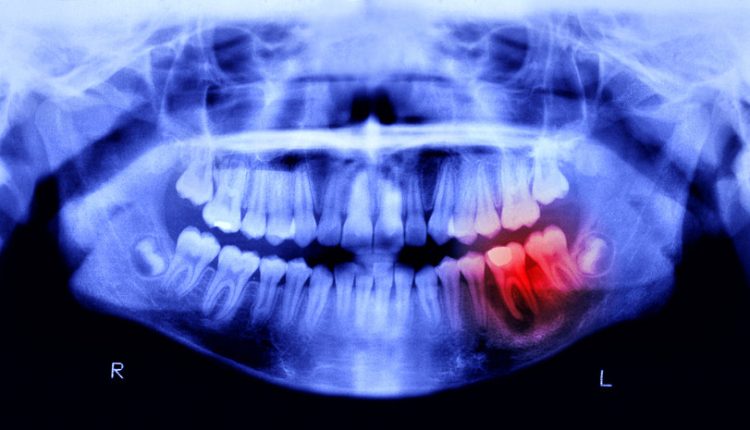

Специалист прокомментировал исследование о связи кариеса с болезнью Паркинсона

Основатель одной из федеральных сетей стоматологических клиник Залим Кудаев рассказал, что новое исследование южнокорейских учёных впервые выявило прямую связь между бактерией Streptococcus mutans, вызывающей кариес, и механизмами развития болезни Паркинсона.

По его словам, при нарушении гигиены полости рта бактерии могут попадать в кишечник, где вырабатывают токсичное соединение имидазол‑пропионат, способное достигать мозга и провоцировать гибель дофаминергических нейронов.

Эксперт добавил, что результаты исследования открывают возможности для профилактики через стоматологическую помощь, а пока клинические приложения находятся в разработке, регулярный уход за зубами становится потенциальным способом защитить мозг.